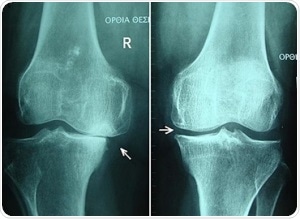

"Gonarthrosis, medial abuse of cartilage" by Scuba-limp [GFDL, CC-BY-SA-3.0 or CC BY-SA 2.5],

via Wikimedia Commons

The study explored numerous significant parameters of bone integrity in bone samples collected from human cadavers. The main parameters were subchondral bone plate thickness, bone mineral density and structural model index that were measured using near-infrared spectroscopy. A dual channel Avantes system combined with the AvaSpec-ULS2048L with the high-sensitivity AvaSpec-NIR256-2.5-HSC was used to record the NIR spectral data.

Spectra were recorded across three wavelength series already recognized for penetrative capabilities in living tissue. This is called the biologic or therapeutic optical window. Firstly, the window covered the range 650-950 nm, then, from 1100-1350 nm, and lastly, the biologic window studied was 1600-1870 nm. This data was correlated against micro-computed tomography results of the same bone samples using partial least squares regression multivariate technique.

Findings showed that an important role was played in the relationship between optical response and subchondral bone properties due to the wavelength-dependent penetration of light into osteochondral samples. The strongest correlation and lowest error rate against the tomography results was identified in the first optial window; λ 650-950 nm. This presents the highest potential for adaptation into arthroscopy standards of care.